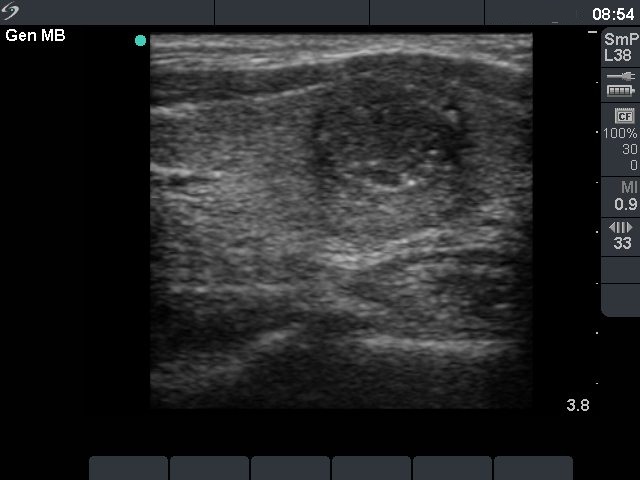

Ultrasonography: there was a hypoechogenic nodule in the ventromedial part of the left lobe. The nodule contained microcalcifications and presented intranodular blood flow.